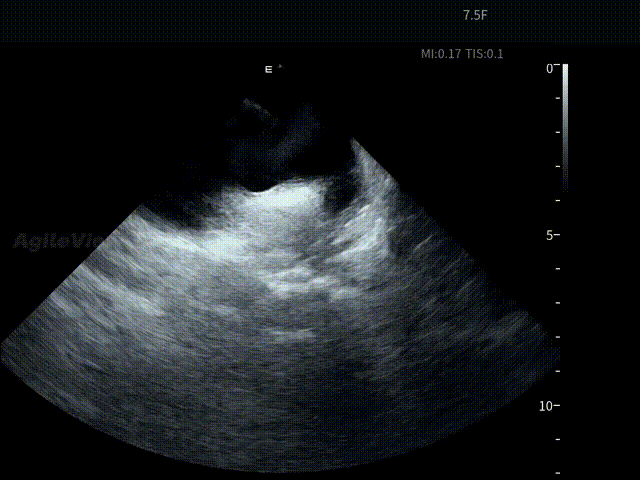

术中,基于AgileView™ 7.5Fr全球最细直径ICE导管的产品优势,周纬教授选择将ICE送入左房,以便更好地进行冷冻球囊的贴靠与位置的判断,在AgileView™ ICE实时影像的指导下, Arctic Front Advance Pro冷冻球囊导管消融导管安全进入左心房,先后完成双侧肺静脉隔离及顶部线隔离, ICE下可见导管贴靠良好,整个消融过程顺利,消融时间仅约25分钟,得益于超声设备清晰的成像质量,在顶部线隔离的时候可借助多普勒模式清晰的观察到球囊与组织的贴靠程度。 整个手术流程在ICE影像的指引下顺利完成,术中患者耐受良好,生命体征保持平稳。

ICE确认LSPV位置——B Mode